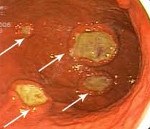

• Язвенную. Лимфомы желудка представляют собой язвы различной глубины. Отличаются наиболее агрессивным течением.

Диагноз устанавливается с учетом жалоб, истории заболевания, внешнего осмотра, пальпации живота, лабораторных и инструментальных исследований. Из-за неспецифичности симптоматики возможно позднее выявление лимфомы желудка, в литературе описаны случаи, когда временной период между появлением болей в эпигастрии и постановкой диагноза составлял около 3 лет. Основным способом инструментальной диагностики является гастроскопия, позволяющая определить расположение и тип роста опухоли. При проведении эндоскопического исследования лимфому желудка может быть трудно дифференцировать с раком, гастритом и немалигнизированной язвой.

Для уточнения диагноза эндоскопист осуществляет забор материала для последующего гистологического и цитологического исследования. Отличительной особенностью взятия эндоскопической биопсии при лимфомах желудка является необходимость забора ткани с нескольких участков (множественная или петлевая биопсия). Для определения распространенности онкологического процесса осуществляют эндоскопическое УЗИ и КТ брюшной полости. Для выявления метастазов назначают МРТ грудной клетки и МРТ брюшной полости. Несмотря на диагностические затруднения, из-за медленного роста большинство лимфом желудка выявляются на первой или второй стадии, что увеличивает вероятность благополучного исхода при данной патологии.